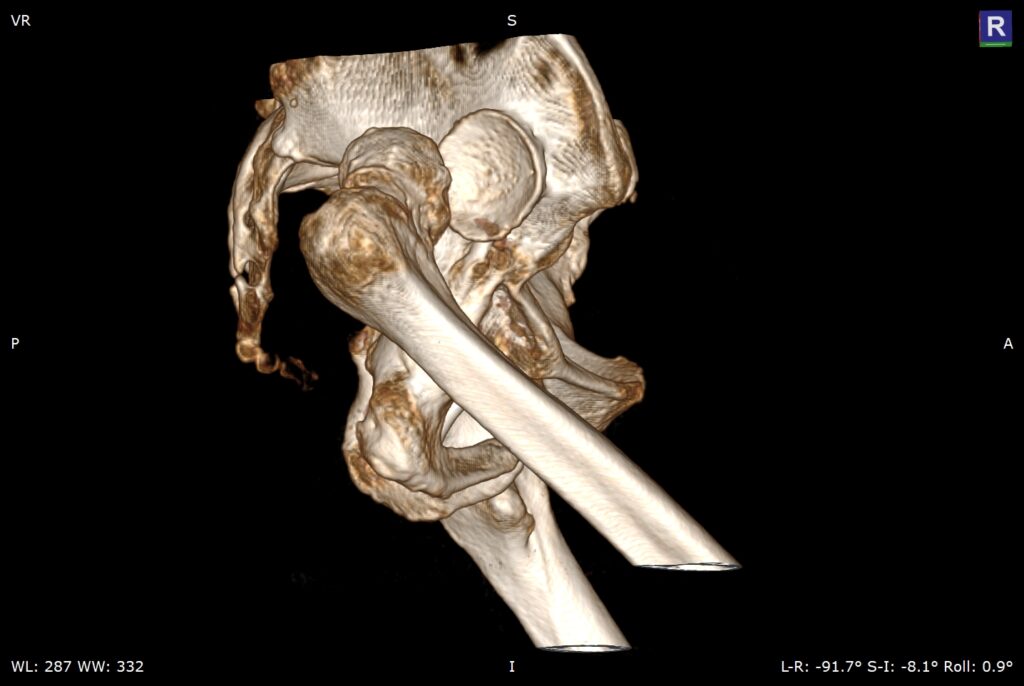

先天性髋关节脱位股骨头在假臼中再脱位(Congenital dislocation of the hip joint leads to re-dislocation of the femoral head in the false socket)